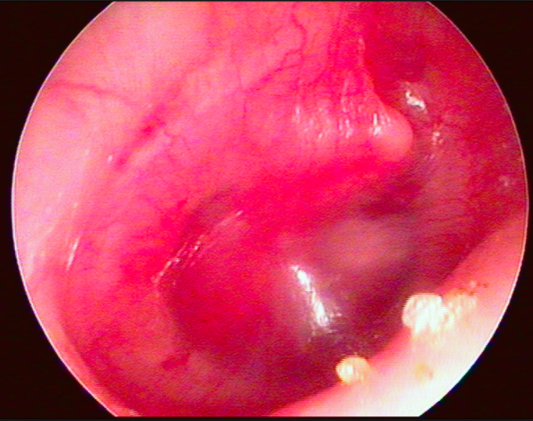

1. Otoscopia

1. Otoscopia neumática (Estándar oro)

1. Timpanometría

1. MT opaca, niveles hidroaéreos o burbujas

2. Otoscopia neumática

1. Hipomotilidad

2. Timpanometría